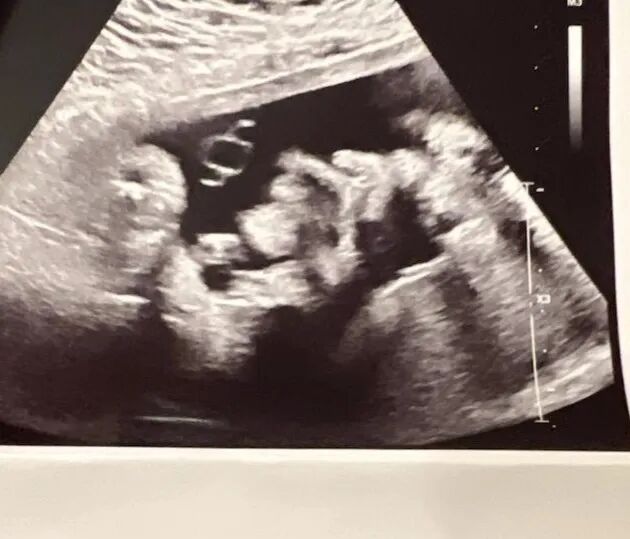

爱S即将迎来宝宝的到来,已经是孕晚期,宝宝已经34周了。在这个阶段,宝宝的发育已经非常接近完成,已经准备好来到这个世界。建议准父母们最晚在爱妈预产期前一周到达,可以陪伴爱妈生产,爱妈通常会把陪伴宝宝生产的名额留给准父母,共同迎接宝宝的重要时刻。

在34周,胎儿的器官和系统已经大部分发育完成,肺部是最后一个成熟的器官之一。此时,肺部已经足够发育,可以进行氧气交换,但仍在持续生产肺表面活性物质,以准备第一次呼吸。此外,大脑也在不断发育,尤其是皮质区域,这是与认知功能相关的关键区域。

胎儿的体重和身长已经相当接近出生时的状态。平均体重约为2.1-2.4千克(4.7-5.3磅),身长约为45-47厘米(17.7-18.5英寸)。胎儿的皮肤变得越来越光滑,但仍带有些许皱纹,因为身体脂肪仍在逐渐沉积,使得体形更加丰满。同时,胎儿的指甲和头发也在不断生长,逐渐完善。

在胎儿发育的这个阶段,他们的运动能力也相对较强。胎儿可能会频繁地翻转、踢动或伸展,这是他们体内神经系统和肌肉系统协调发展的表现。尽管胎儿已经接近成熟,但在接下来的几周内,他们的身体仍将继续成熟和发育,为出生做好最后的准备。